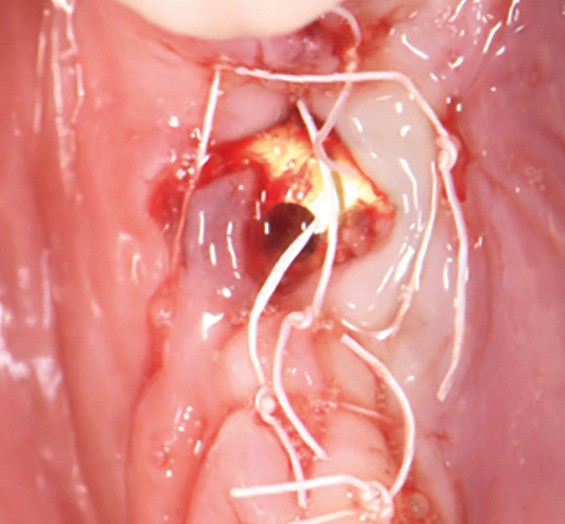

Actes préopératoires

La couronne a été déposée et une vis de couverture mise en place. La patiente a reçu un nettoyage supra-gingival général avec une attention particulière pour l’implant 47, et une irrigation locale avec du gel de chlorhexidine et du peroxyde d’hydrogène pour réduire l’inflammation des tissus. De l’amoxicilline (3 x 500 mg) a été prescrite, à commencer la veille de l’intervention chirurgicale.

La patiente est restée 4 semaines sans couronne. Après l’intervention chirurgicale, elle a entamé un programme de soins péri-implantaires et parodontaux, avec des visites de rappel tous les 4 mois.